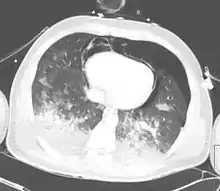

Computed tomography

Computed tomography (CT scanning) is a more sensitive test for pulmonary contusion,[6][33] and it can identify abdominal, chest, or other injuries that accompany the contusion.[38] In one study, chest X-ray detected pulmonary contusions in 16.3% of people with serious blunt trauma, while CT detected them in 31.2% of the same people.[45] Unlike X-ray, CT scanning can detect the contusion almost immediately after the injury.[43] However, in both X-ray and CT a contusion may become more visible over the first 24–48 hours after trauma as bleeding and edema into lung tissues progress.[46] CT scanning also helps determine the size of a contusion, which is useful in determining whether a patient needs mechanical ventilation; a larger volume of contused lung on CT scan is associated with an increased likelihood that ventilation will be needed.[43] CT scans also help differentiate between contusion and pulmonary hematoma, which may be difficult to tell apart otherwise.[47] However, pulmonary contusions that are visible on CT but not chest X-ray are usually not severe enough to affect outcome or treatment.[37]